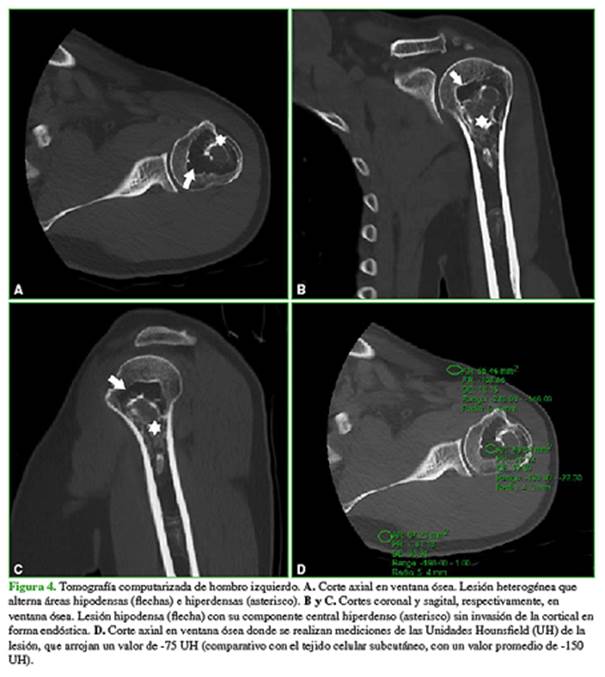

La articulación acromioclavicular presenta cambios degenerativos con disminución del espacio acromiohumeral. Se observa la rotura de espesor completo del tendón del supraespinoso, con retracción miotendinosa. Se sugiere completar el estudio con una tomografía computarizada (Figura 4).

Tomografía computarizada: Lesión intraósea con atenuación grasa.